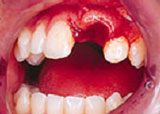

Injuries to teeth and surrounding tissues can be very distressing for the person involved as well as the parents, when a child is involved. Dental trauma may occur as a result of a sports mishap, an altercation, a fall inside of the home, or other causes. Prompt treatment is essential for the long-term health of an injured tooth.

Obtaining dental care as soon as possible, even if via phone call, can make the difference between saving or losing a tooth.